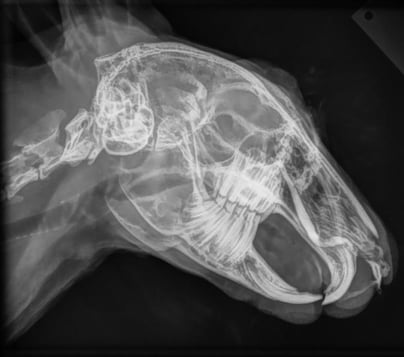

Wir arbeiten mit einem digitalen Röntgengerät der neusten Generation und können Ihnen die Röntgenbilder ihres Tieres sofort nach der Aufnahme auf dem Computer zeigen. Wir bieten alle gängigen Röntgenuntersuchungen sowie offizielle HD-/ED-Aufnahmen an.